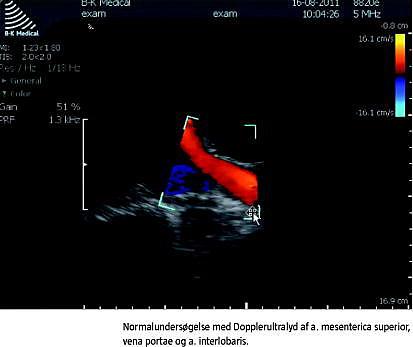

Nedenfor er givet eksempler på undersøgelser af abdominale kar med Dopplerultralyd. Ved undersøgelserne er der benyttet en lavfrekvent kurvet abdominaltransducer, og B- mode -billedet er optimeret mht. dybde, gain og fokus.

Arteria mesenterica superior

I faste har arteria mesenterica superior plug flow med en trifasisk profil, som ligner den i aorta abdominalis med hurtige op- og nedslag i systolen (Figur 3 ). Plug flow opstår, når blodet har omtrent samme hastighed, hvad enten det befinder sig i centrum eller mere perifert i karlumen. Spektralkurven er derfor skarpttegnet og overvejende uafhængig af range gate -bredde [4, 7]. Den trifasiske flowprofil skyldes, at der i tidlig diastole er et retrogradt flow og i sen diastole et antegradt flow. Efter fødeindtag sænkes modstanden i karret, og en øget maksimal systolisk hastighed (PSV) og slutdiastolisk hastighed (EDV) indtræder med udelukkende positivt flow i diastolen for at imødegå det øgede iltkrav fra tarmen. Flowprofilen ændres fra plug flow til laminart flow, der er kendetegnet ved faldende hastigheder i lumen fra centrum mod periferien, hvilket resulterer i en bredere spektralkurve [6, 8]. Ved betydende stenose i arteria mesenterica superior som ved kronisk intestinal iskæmi ses hos fastende patienter PSV > 275 cm/s, som øges yderligere postprandialt, samt EDV > 50 cm/s. Normalværdien ved faste er for PSV 130 (± 18) cm/s og EDV 24 (± 4) cm/s [7].

Vena portae

Flowet i vena portae estimeres med transduceren placeret interkostalt i patientens højre flanke. Herved opnås en brugbar insonationsvinkel, og overlejrende tarmluft undgås. Ved normalt flow i vena portae vil farve-Doppler inden for colour box vise antegradt (hepatopetalt) flow. Dvs. at flow i det portale system, der løber ind i leveren ved interkostal skannerposition, derfor bevæger sig mod transduceren. Range gate placeres i lumen og indstilles tilstrækkeligt smal, så signal fra arteria hepatica, der forløber i tæt relation hertil, undgås. Flowet er positivt og laminart med hastigheder på 20-40 cm/s. Der ses en diskret fasisk bevægelse i flowet synkront med hjertefrekvensen, hvilket skyldes tilbagetransmitterede trykændringer fra højre atrium via levervenerne, og en langsommere fluktuation, som skyldes respirationssynkrone trykændringer i thorax (Figur 3) [5].

Nyrekar

Nyren skannes fra flanken. Organet gennemgås i længde- og tværskanning med farve-Doppler. PRF sættes så lavt, at små kar kan visualiseres, og et indtryk af ensartet perfusion opnås. Dernæst udvælges en intrarenal interlobær arterie til spektral-Doppler-estimering. Når nyrens interlobære arterier skannes fra flanken, vil insonationsvinklen være optimal, og flowet vil have retning mod transduceren. Til evaluering af nyren hører beregning af det resistive indeks (RI), der er givet ved:

RI er en ratio, dvs. uden benævnelse og følgelig vinkeluafhængig. RI, der beregnes ud fra spektrogrammet og ofte automatisk af skanneren, er et udtryk for karrets komplians og modstand. Normalværdien for RI er 0,60-0,70 [6, 9] (Figur 3).